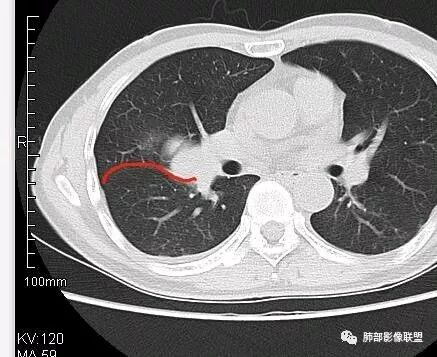

南边:从叶裂的变形,下朝上,越来越朝前扭曲,提示叶裂局部有朝前上推移的趋势

南边:下叶的支气管受压后移、变形

南边:病灶边界清,提示侵袭性弱,膨胀生长为主;这时候我们提示病灶不应该是支气管关系密切,提示间叶来源或胸膜来源

深分叶,警惕恶性

常规考虑:1、肉瘤首先考虑

2、胸膜孤立性纤维瘤待排